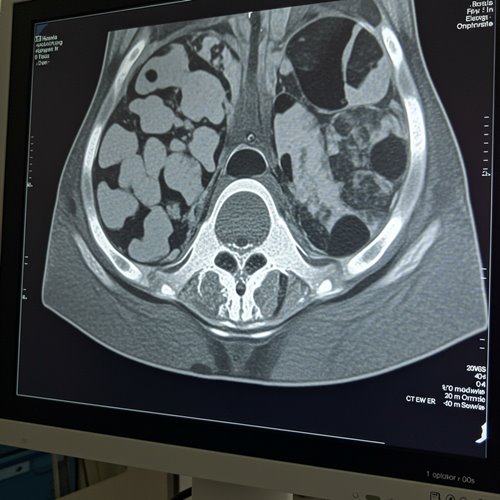

- 영상 검사: CT, MRI 등을 통해 암의 크기와 전이 여부를 평가합니다.

4기는 암이 간, 폐 등 다른 장기로 전이된 상태입니다. 이 경우 완치보다는 생존 기간 연장과 삶의 질 유지가 치료 목표가 됩니다. 항암치료가 중심이 되며, 일부 환자에서는 전이 병소에 대한 절제 수술이나 고주파 열치료 등 국소치료가 병행될 수 있습니다. 최근에는 표적 치료제나 면역치료 등도 일부 적용되고 있습니다.